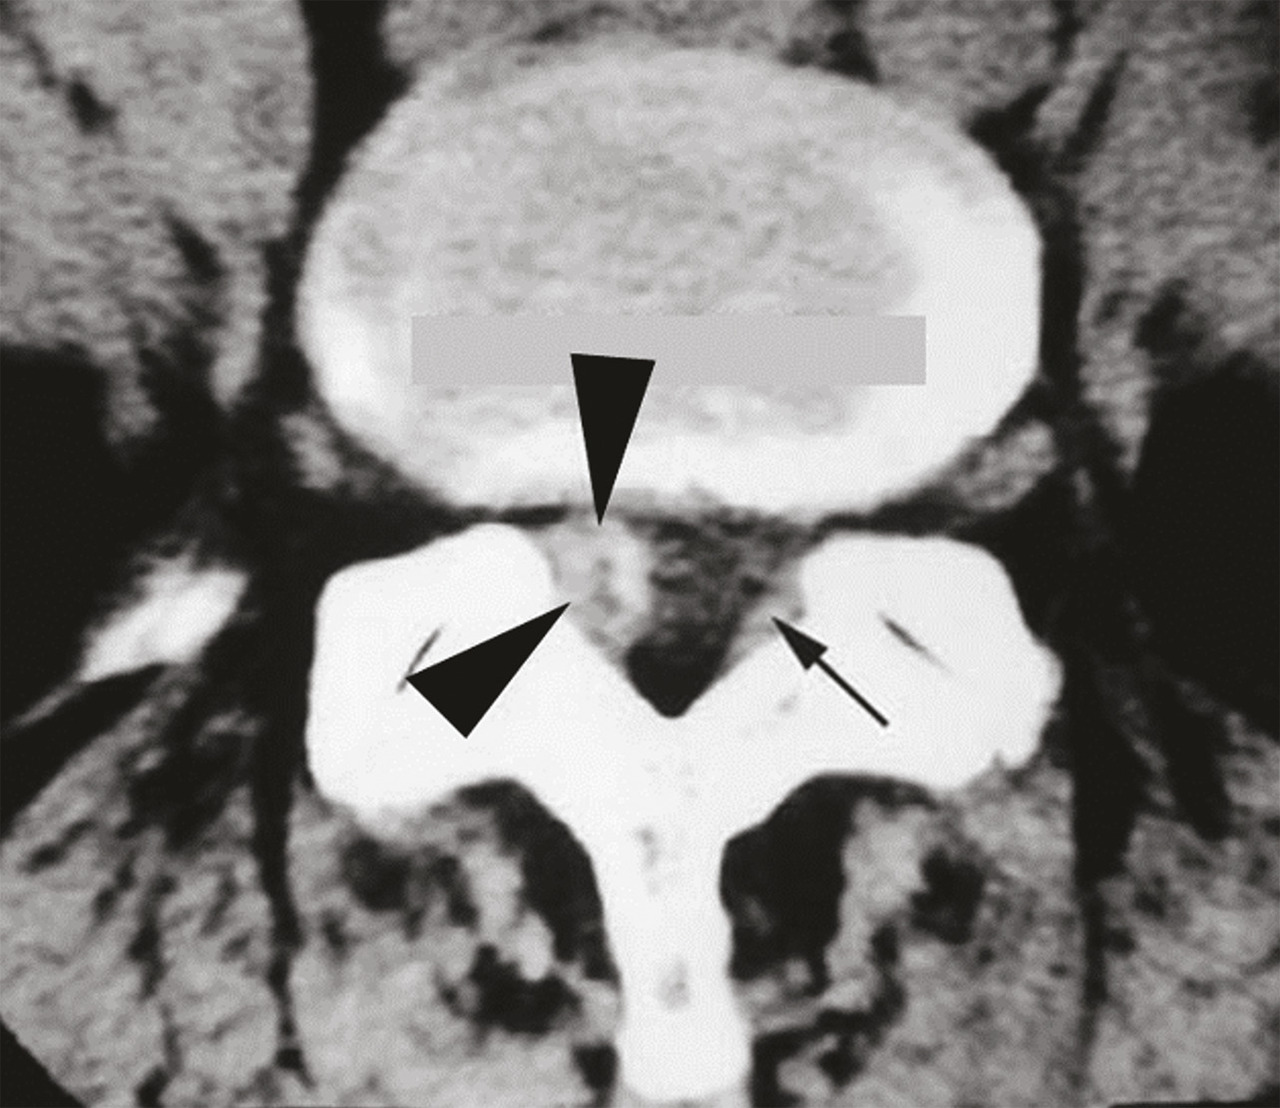

Spécificités du kyste synovial articulaire postérieur

Un kyste synovial développé aux ­dépens d’une articulation interapophysaire postérieure peut provenir de l’arrière et comprimer l’émergence d’une racine nerveuse (fig. 3). Il constitue une cause relativement fréquente de lomboradiculalgie du sujet d’âge mur. Ce kyste se développe à partir d’une arthropathie postérieure dégénérative, habituellement érosive, et est associé dans deux tiers des cas à un spondylolisthésis dégénératif.9 Une injection de corticoïdes dans l’articulation postérieure à l’origine du kyste permet de faire céder durablement la radiculalgie dans un tiers des cas. En revanche, si la radiculalgie persiste ou récidive sous bref délai (< 6 mois), de nouvelles injections sont, en règle générale, inefficaces. Il faut donc recourir à l’exérèse chirurgicale du kyste, parfois associée à une stabilisation, s’il existe des signes d’instabilité vertébrale.9